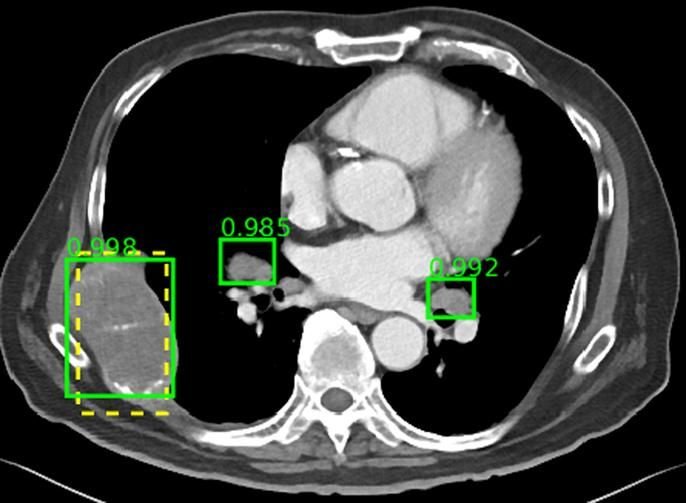

La segmentación automática es una innovación clave de AI en imágenes de oncología con una precisión mejorada de contorneado para órganos en riesgo (OAR) en la planificación de la radioterapia, eliminando la variabilidad interobservador y mejorando la eficiencia del trabajo. Como ejemplo, Tang et al. propuso una herramienta basada en el aprendizaje profundo para proporcionar de forma semiautomática los criterios de evaluación de respuesta en tumores sólidos (RECIST), que actualmente se utiliza como una medida estándar de la extensión del tumor para evaluar el tratamiento de los pacientes. Se demostró que el sistema no se ve afectado por la variabilidad entre lectores al tiempo que demuestra un acuerdo prometedor con el consenso de los RadioOncólogos.